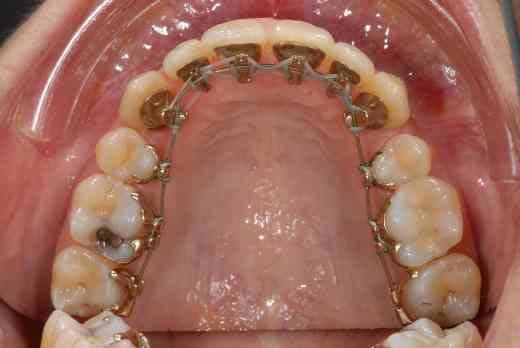

voilà quelques roros et un an plus tard...

elle est merdique hein ma 12, décidément je m'en remets pas de cette 12 :-(((

Fait ouvrir tes espaces pré-molaires

ensuite implants. Ton ortho, c'est le même qui place des implants bizarre ?

J’aurais tendance à penser comme val en ce qui concerne ta classe II, mais ce qui me turlupine le plus dans ton cas, Doc, c’est la différence de hauteur des collets des incisives apparue pendant le traitement.

La ligne des collets ne semble pas trop mauvaise sur la photo d’avril, ce n’est malheureusement plus le cas sur celle de décembre, où le collet de la 11 apparaît plus bas que celui de la 12.

Comment ton orthodontiste compte-t-elle gérer cela ?

sinon arrêtez avec la chir, j'ai dit non, j'ai dit non....bientôt c'est les mini-vis....:-(